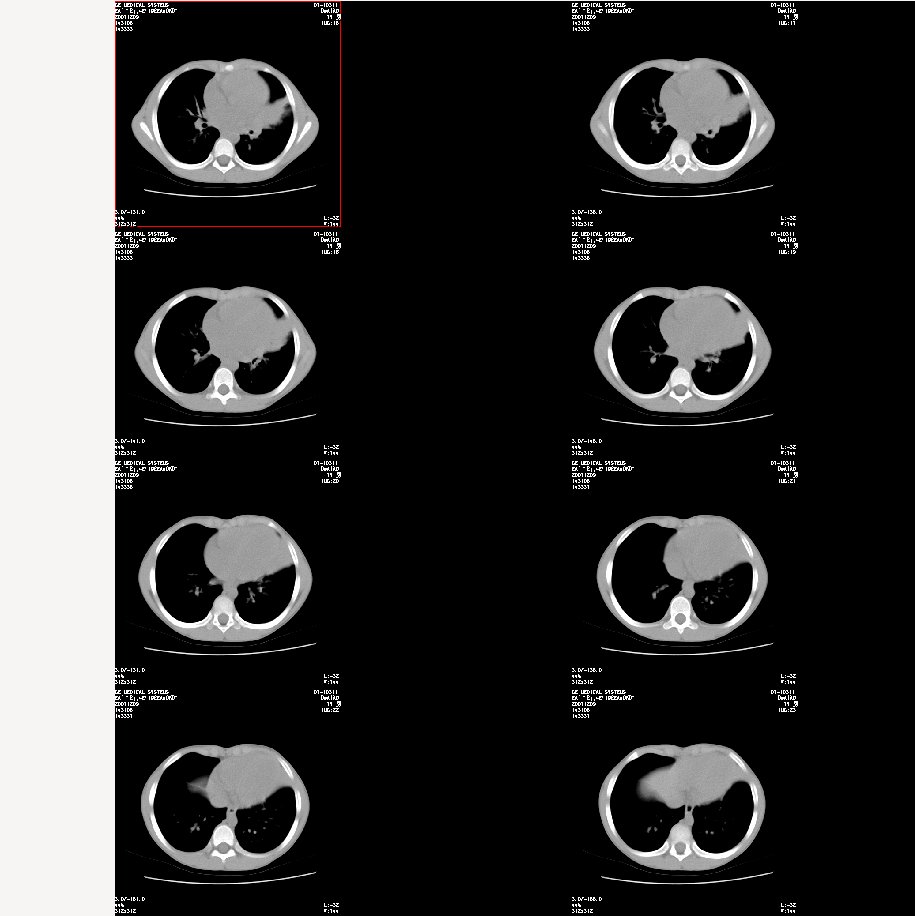

双肺感染性病变——结核可能性大!

首先考虑肺内炎症。

支持肺炎,建议严格抗炎治疗后复查。

炎症应该有,排除一下有没有支扩吧

左肺上叶上舌段不张实变,建议纤支镜检查

左肺炎症,是否为过敏性。

支持 肺发育不全伴感染与支气管扩张

考虑肺炎,但支气管会不会有问题,建议抗炎治疗后复查。